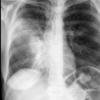

Case 2 Lingular pneum PA

Date: 04/17/2005

Views: 5799